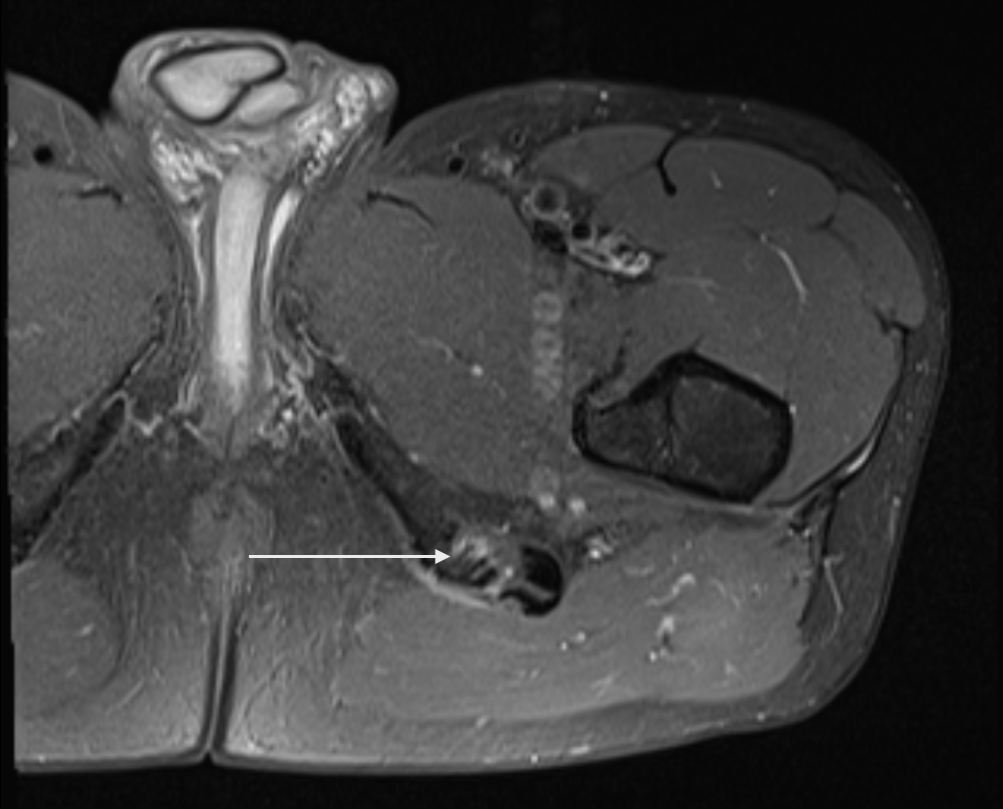

Consent✅ 1 year progressive severe (painless) L calf atrophy & weakness Medial bulk affected > lateral - see pic Affecting football performance Rolling over in bed onto R side - sudden 'spasms' in leg leg US - diffuse fatty atrophy of medial gastroc & soleus (vs R) EMG / NCS - severe L5 & S1 subacute chronic radiculopathy MRI - no herniated disc - but 5cm filum terminale lipoma (high signal on T1 seq, low on STIR). Also very low lying conus medullaris & tethered cord suggestive of spinal dysraphism (spina bifida occulta) Neurosurgical referral